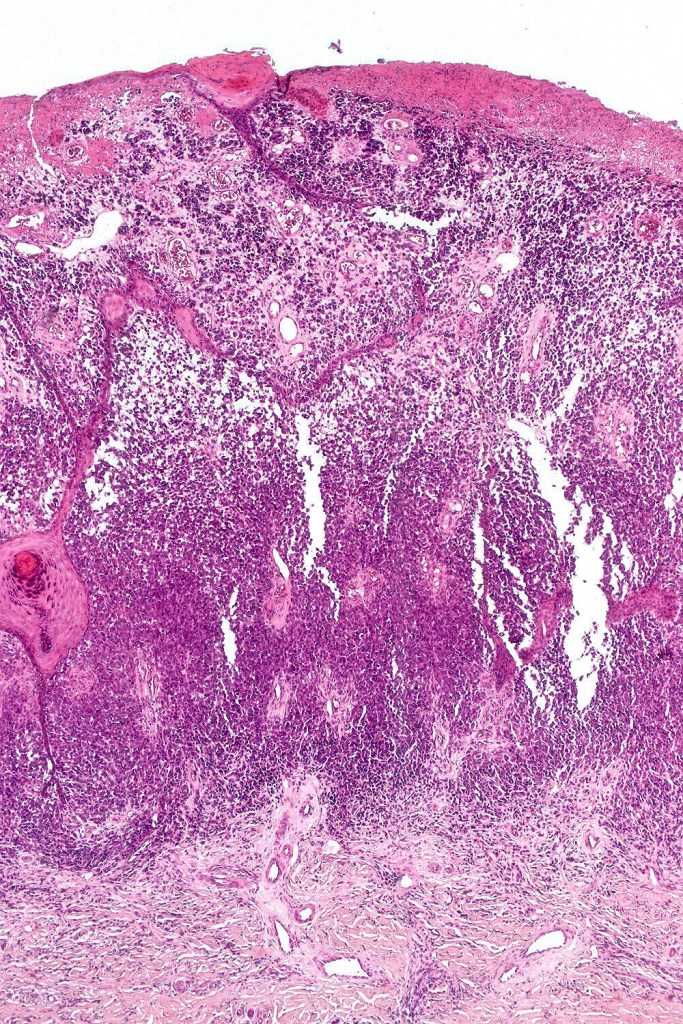

A rare variant of nevoid melanoma wherein the tumor cells have scant cytoplasm, and basophilic, hyperchromic nuclei mimicking type B nevus cells. Typically, the tumor cells are positive for S100, Mart-1 & HMB45. It is of no prognostic importance. It is one of the more often encountered melanoma variants in giant congenital nevi & can be mistaken for a congential nevus if the lesion is dismissed as benign at scanning magnification. In the absence of clinical history in metastatic lesions, the differential diagnoses of lymphoblastic leukemina/lymphoma, neuroendocrine carcinoma, small cell carcinoma, neuroblastoma, malignant perihperal nerve sheath tumor & Ewing’s sarcoma can be excluded with appropriate immunohistochemistry. Exceptionally small cell melanoma may express neuroendocrine markers